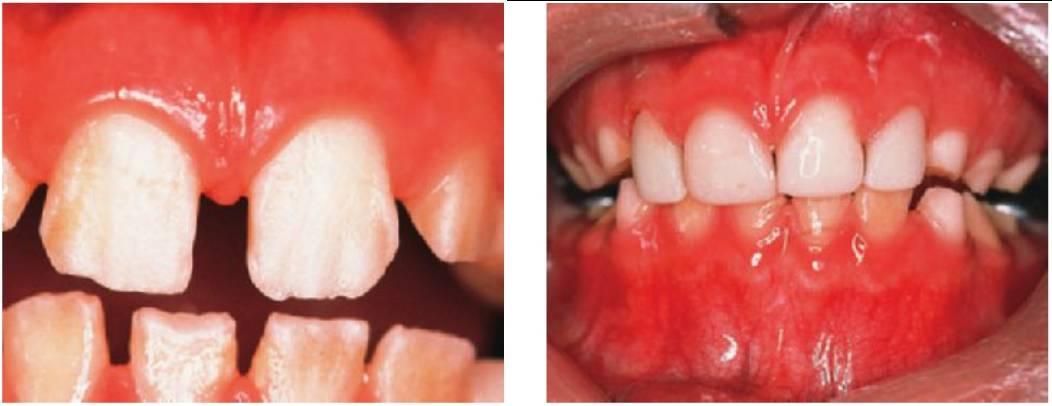

Amelogénesis imperfecta

El término amelogénesis imperfecta (fig. 9.25) suele aplicarse a defectos hereditarios del esmalte que afectan tanto a los dientes temporales como a los permanentes. La definición implica una historia familiar, pero en la práctica parece razonable ampliar esta definición para incluir los casos esporádicos y aquellos otros en los que los defectos del esmalte se asocian a manifestaciones extraorales, como ocurre en algunos síndromes (es decir, hipoplasia dérmica focal o síndrome trico-dento-óseo).

Fenotipos

Los fenotipos oscilan desde el esmalte (fino) marcadamente hipoplásico, uniformes (con espacios entre los dientes) o irregulares (dando lugar a pozos o surcos) hasta los diferentes grados de hipomineralización (esmalte muy mal formado) con alteraciones en su color y traslucidez. En muchos casos, la hipoplasia y la hipomineralización se presentan juntos. El color del esmalte refleja con claridad el grado de hipomineralización del mismo: cuanto más oscuro se presente el tono, más grave será la desmineralización.

En la amelogénesis imperfecta ligada al cromosoma X, las mujeres presentan franjas ver ticales de esmalte alterado como signo de lyonización (v. hipótesis de Lyon, descrita en este mismo capítulo). Pueden ser surcos verticales (debido a la hipoplasia) y/o bandas verticales de esmalte con el color o lucidez alterados (debido a la hipomineralización), o bien una combinación de ambos. En estas familias no existirá transmisión de varón a varón, pero las mujeres heterocigóticas pueden transmitir el rasgo a niños del mismo sexo.

En algunos pacientes afectados por amelogénesis imperfecta, los dientes no llegan a erupcionar, se cree que debido a una alteración del órgano del esmalte y sufren una reabsorción de sus coronas. En algunos casos (más del 50%) se observa una mordida abierta esquelética anterior.

Formas predominantes/exclusivas de hipomineralización del esmalte

- El esmalte tiene un espesor normal, al menos inicialmente.

- El color es amarillo o pardo.

- El esmalte es más blando de lo normal, tiende a astillarse y se puede atravesar con un explorador. En los casos muy hipomineralizados, se puede arañar el esmalte con una cureta.

- Los dientes pueden erupcionar con un espesor normal, pero el esmalte se pierde pronto, dejando al descubierto una dentina rugosa y muy sensible.

- Se forman grandes masas de cálculo supragingival.

Tratamiento

- Compromiso de apoyo permanente a los niños y las familias. Se trata de cuadros dolorosos que desfiguran al niño y lo convierten en objeto de burla.

- Preservación de los molares con restauraciones de recubrimiento total para mantener la dimensión vertical. Las sobredentaduras pueden resultar una opción en niños con dientes hipoplásicos pequeños (fig. 9.27E, F).

- Coronas de acero inoxidable u onlays de oro en los molares (fig. 9.28). También puede resultar eficaz la elaboración de coronas, de composite en el laboratorio.

- Carillas de composite en los dientes anteriores para conseguir una buena estética. Se puede adherir con éxito resina composite a un esmalte hipoplásico e hipomineralizado (figs. 9.27 y 9.28).

- Puede resultar difícil conseguir unos márgenes adecuados debido a la mala calidad del esmalte (fig. 9.28C).